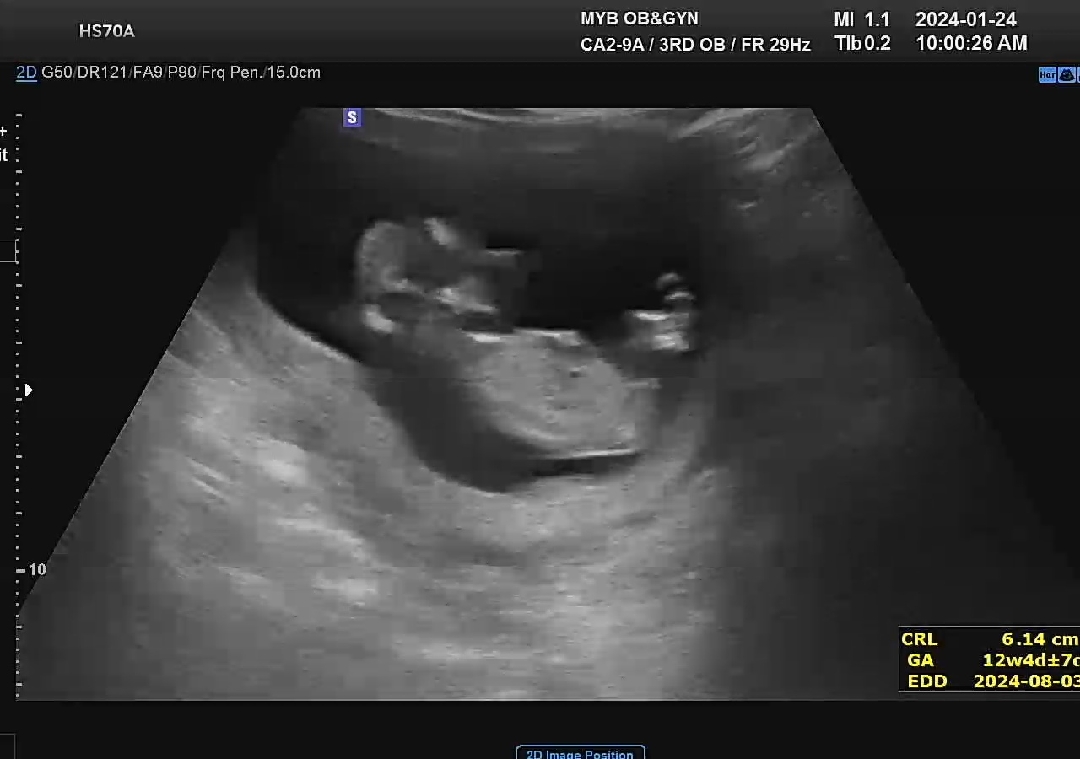

아들일까요?딸일까요?

태몽은 다 딸이였고 아들증상과 정반대증상인데 의사선생님이 애매한지 확답은 못주시더라고요~ 고수님들 봐주세요~

ㅎㅎ많이 나뉘네요! 다리사이에서는 보인락말락해서 올려보았어요ㅎ